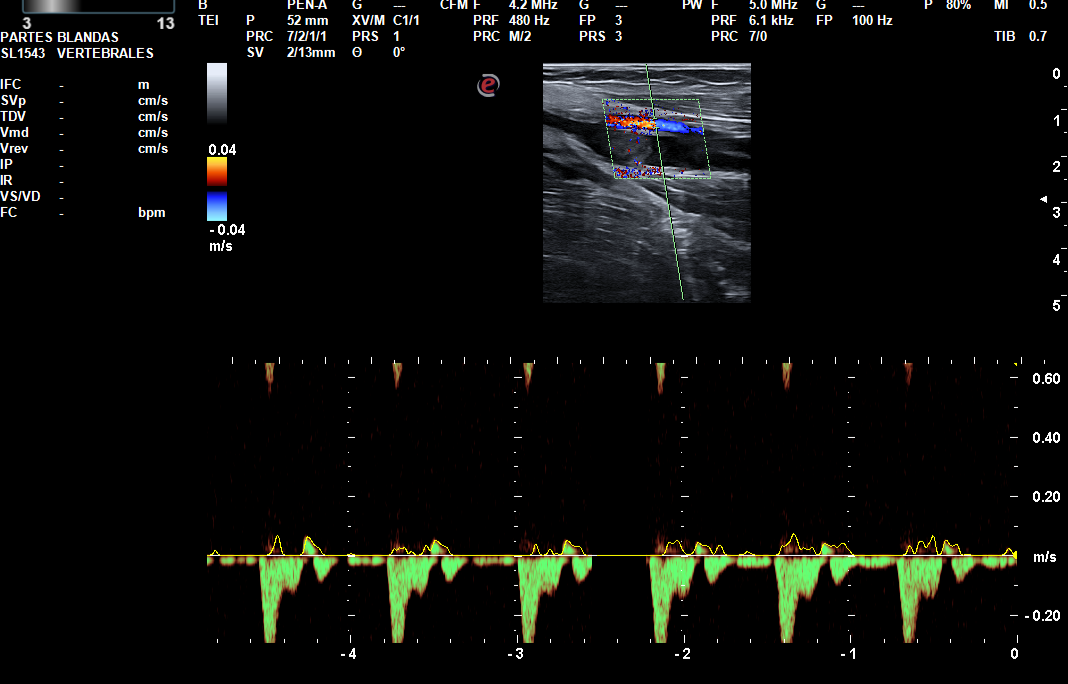

Hallazgos ecográficos

Trombo flotante en la confluencia yugulosubclavia. Ocupación por material hipoecogénico sugerente de trombosis venosa aguda, de la vena subclavia y ramas tributarias regionales, vena axilar, confluencia entre la vena cefálica (trombosada solo en su segmento más proximal a la confluencia) y axilar, así como de las venas braquiales hasta el codo.

Por otro lado, este caso resulta de especial interés, pues una vez más, la ecografía clínica, resultó clave para su posterior estudio, convirtiéndose esta técnica en un brazo de extensión y apoyo con el que puede contar el Médico de Atención Primaria.